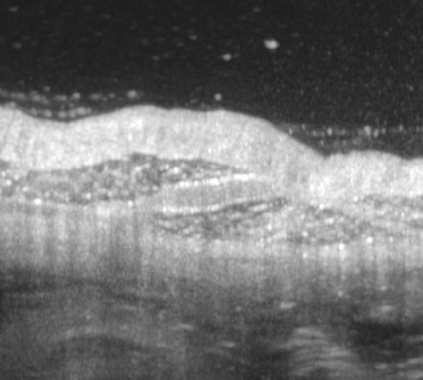

The statistical supervised learning framework assumes an input-output set with a joint probability distribution that is reliably represented by the training dataset. The learner is then required to output a prediction rule learned from the training dataset's input-output pairs. In this work, we provide meaningful insights into the asymptotic equipartition property (AEP) \citep{Shannon:1948} in the context of machine learning, and illuminate some of its potential ramifications for few-shot learning. We provide theoretical guarantees for reliable learning under the information-theoretic AEP, and for the generalization error with respect to the sample size. We then focus on a highly efficient recurrent neural net (RNN) framework and propose a reduced-entropy algorithm for few-shot learning. We also propose a mathematical intuition for the RNN as an approximation of a sparse coding solver. We verify the applicability, robustness, and computational efficiency of the proposed approach with image deblurring and optical coherence tomography (OCT) speckle suppression. Our experimental results demonstrate significant potential for improving learning models' sample efficiency, generalization, and time complexity, that can therefore be leveraged for practical real-time applications.